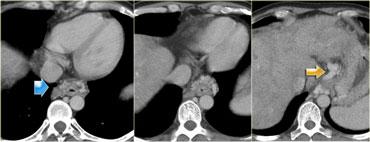

Hãy mô tả hình ảnh bên trái.

Sau đó tiếp tục.

Trên phim X-quang ngực tư thế thẳng AP của bệnh nhân này, có hình ảnh giãn rộng ngách azygos-thực quản bên phải.

Có hình ảnh giãn rộng rõ ràng của đường cạnh sống bên trái.

Trên phim nghiêng, khối nằm phía trước cột sống và do đó được xác định nằm ở trung thất giữa.

Trên CT, ngách azygos-thực quản bị đẩy lệch sang phải do giãn tĩnh mạch thực quản (mũi tên xanh) và cũng xuất hiện một đường ranh giới mới ở bên trái.

Đây là bệnh nhân xơ gan với giãn tĩnh mạch do tăng áp lực tĩnh mạch cửa.